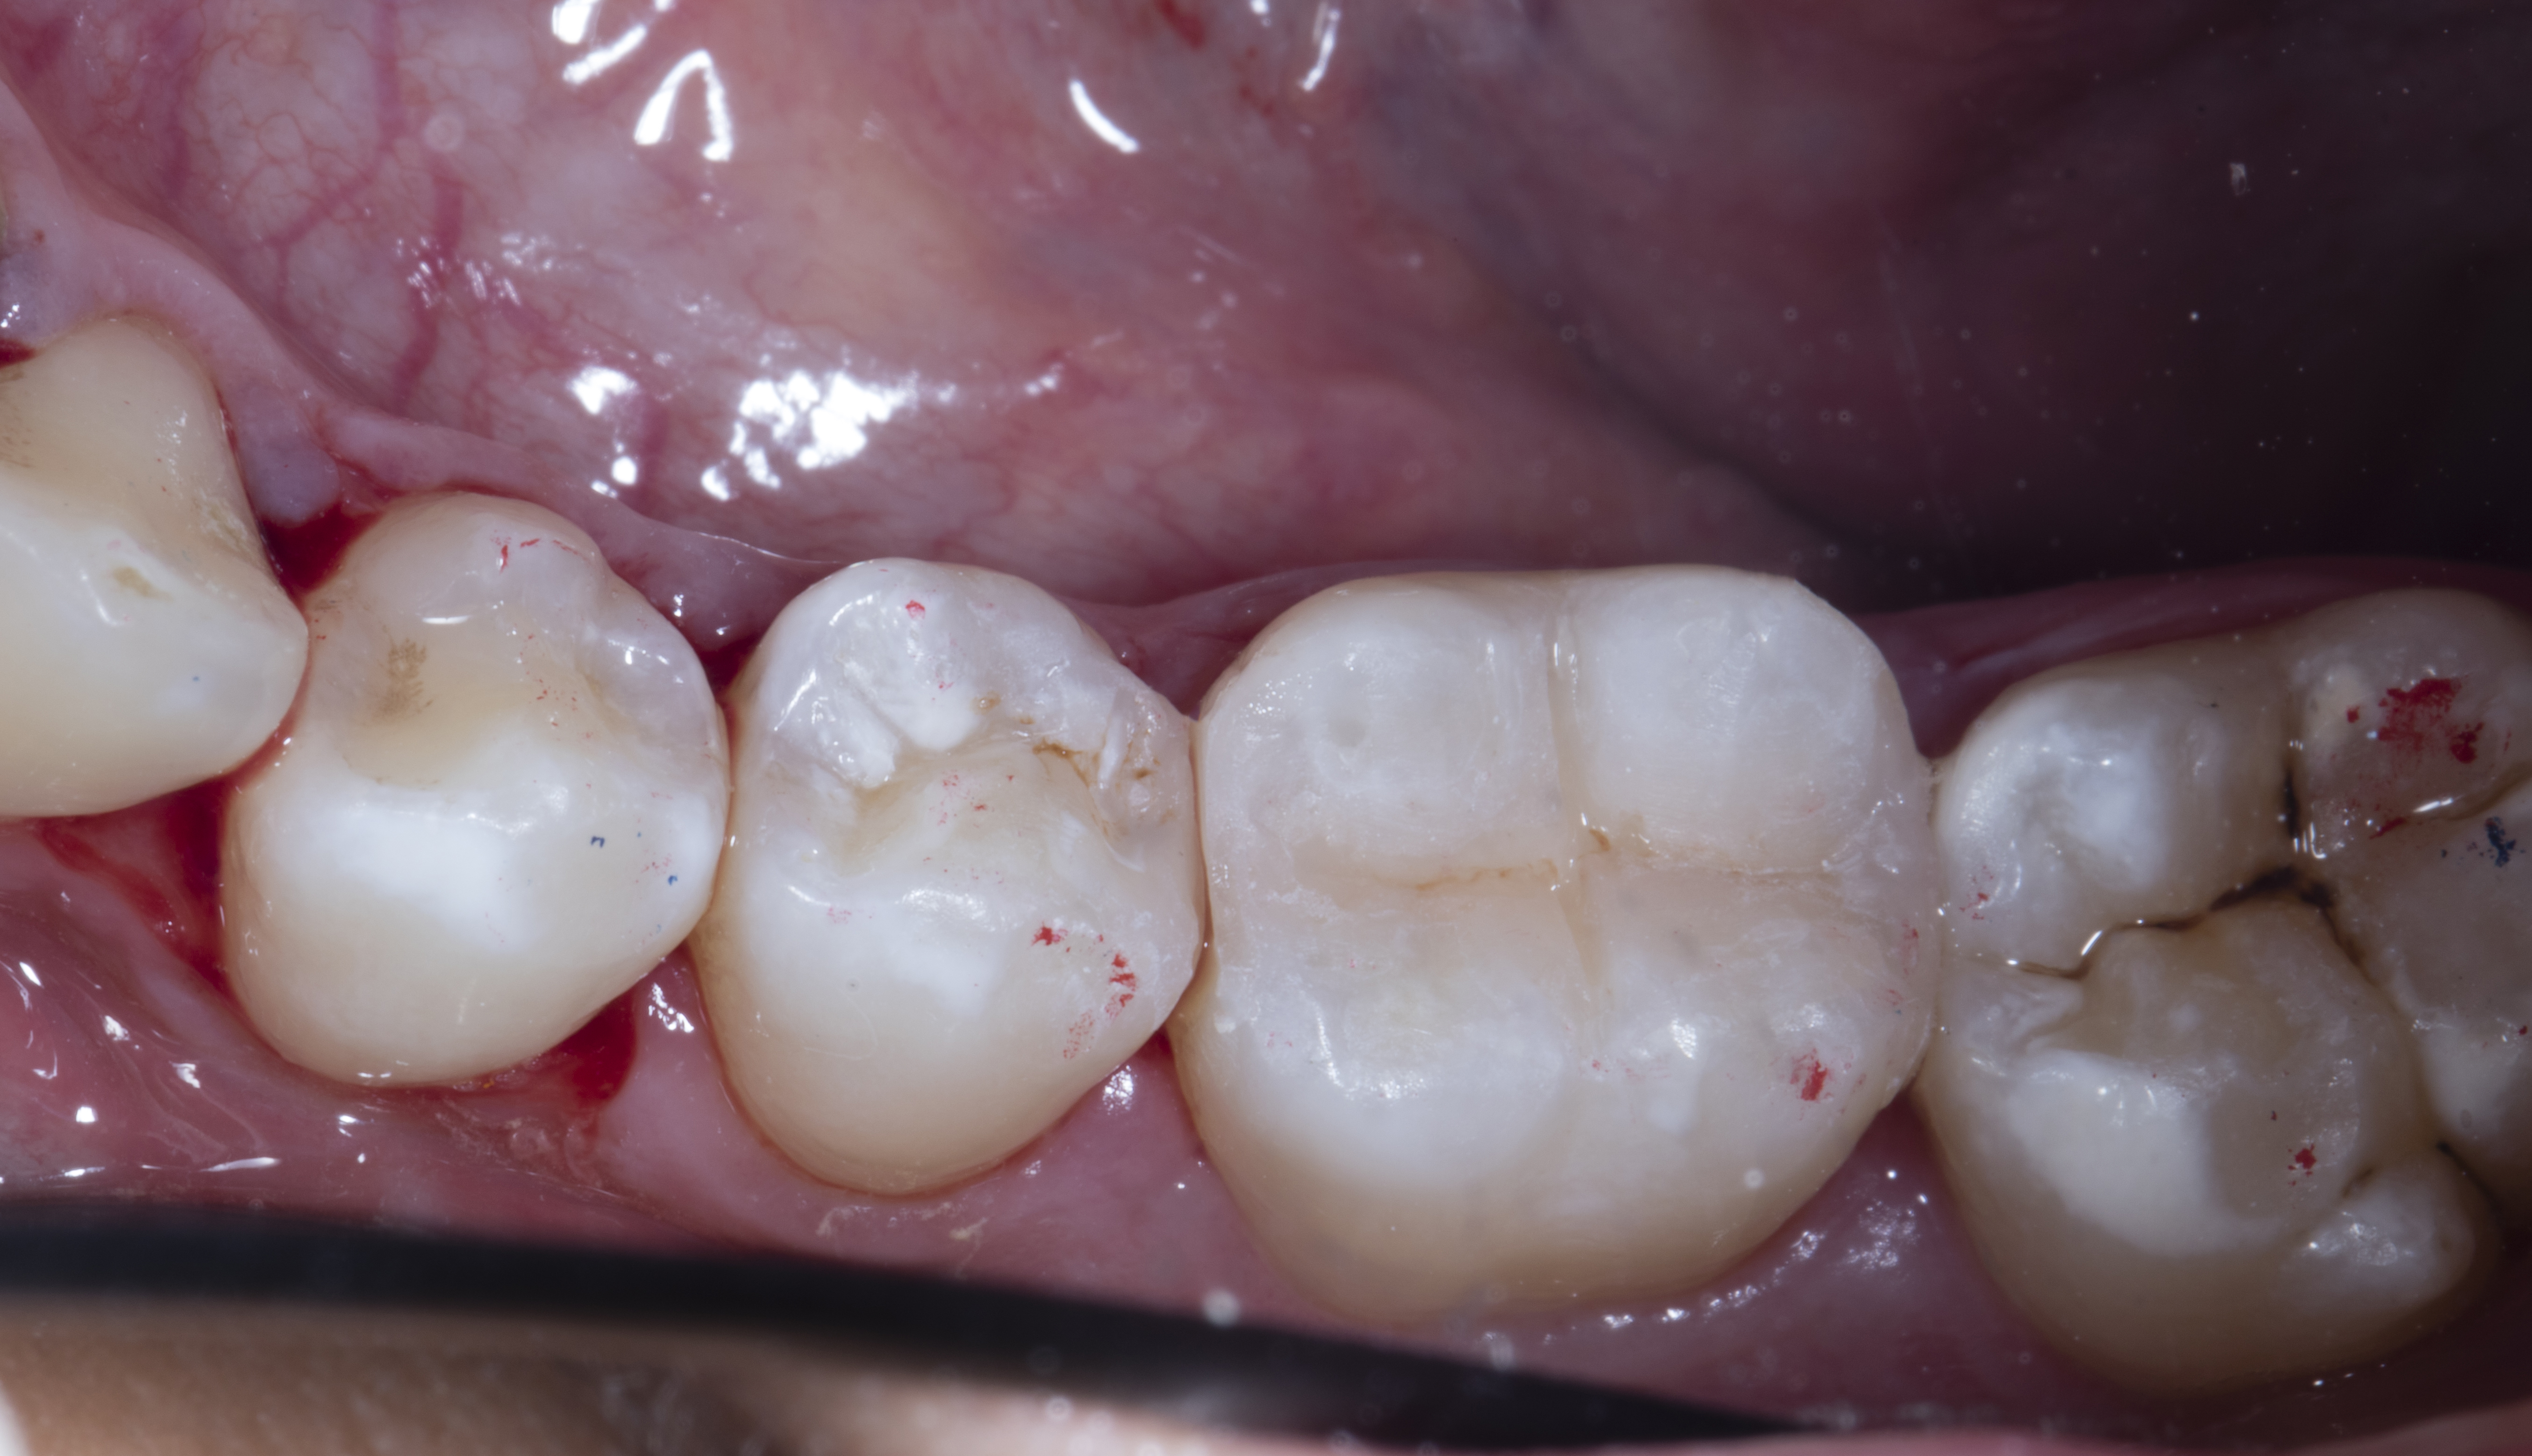

Step 11 – The rubber dam was removed and occlusion checked with 40 micron articulating paper in static occlusion and again in dynamic occlusion with patient in upright position.

Figure 11

Figure 11. Rubber dam was removed and occlusion checked with 40 micron articulating paper in static occlusion.

Step 12 - Finishing and polishing was done using Shofu OneGloss, aluminium oxide impregnated silicone polisher.  A Super Buff disk was used after soaking in water for 20-30 seconds to achieve the final high gloss.

Figure 12

Figure 12. After finishing and polishing.